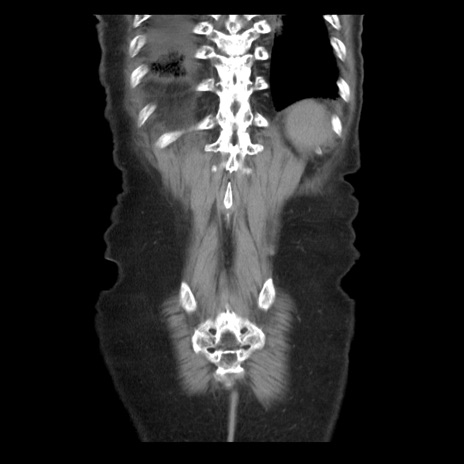

症例21(冠状断像)

【症例】70歳代男性

【主訴】腹痛

【現病歴】肝硬変・肝細胞癌にてかかりつけの方。約9時間前に食後より腹痛出現。症状が徐々に増悪し、嘔吐出現したため来院。

【既往歴】肝硬変、肝細胞癌(RFA、TACE後)

【身体所見】意識清明、表情苦悶様、BT 36℃、BP 129/78mmHg、P 88bpm、SpO2 97%(RA)、右上腹部から心窩部にかけて圧痛あり、反跳痛なし、筋性防御あり。

【データ】WBC 5800、CRP 0.16